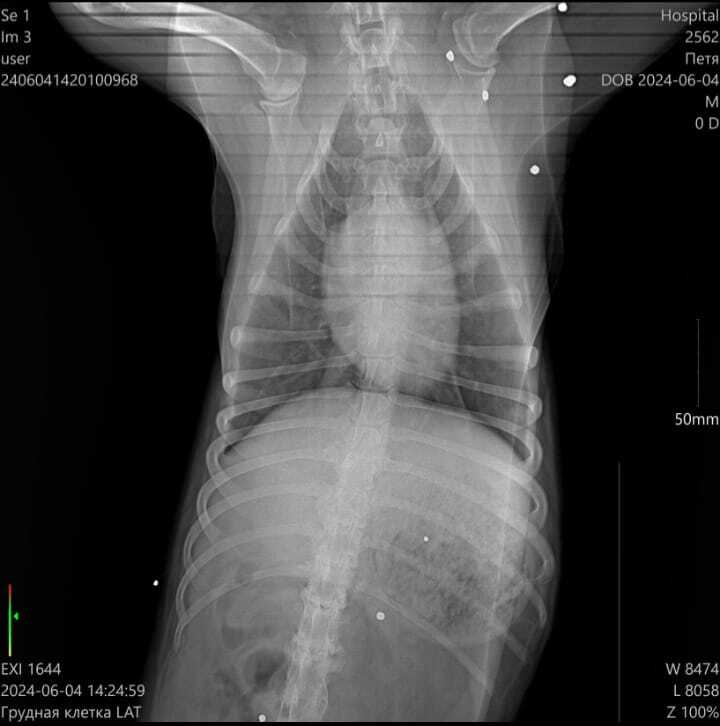

Друзья, в поселке Петрово живодёры стреляли в собаку. Бедный парень спрятался, пока люди не заметили, что с ним совсем беда. Состояние критическое: дробь в лапах, груди, морде; неизвестно, удасться ли сохранить одну из особо повреждённых лапок; множество травм по телу; некоторые ткани отмирают на глазах. Слов не хватает  описать весь ужас.

В данный момент за жизнь собаки борятся в клинике "Кранц Мур" в Зеленоградске. Нужна срочная помощь!